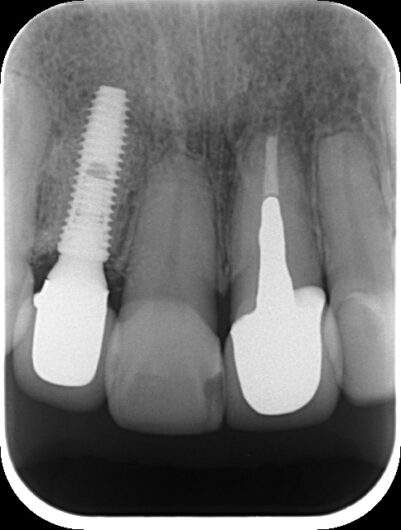

「前歯が折れてしまい、歯科医院で“抜歯しかありません”と言われました。本当に抜かないといけないのでしょうか?」5年前、50代の女性がセカンドオピニオンとして来院されました。前歯の抜歯は見た目や会話、食事に直結するため、強い不安を感じやすい状況です。 初診時の状態と診断 前医では「歯が横に割れているため抜歯」と診断されていました。当院で精査したところ、レントゲ …